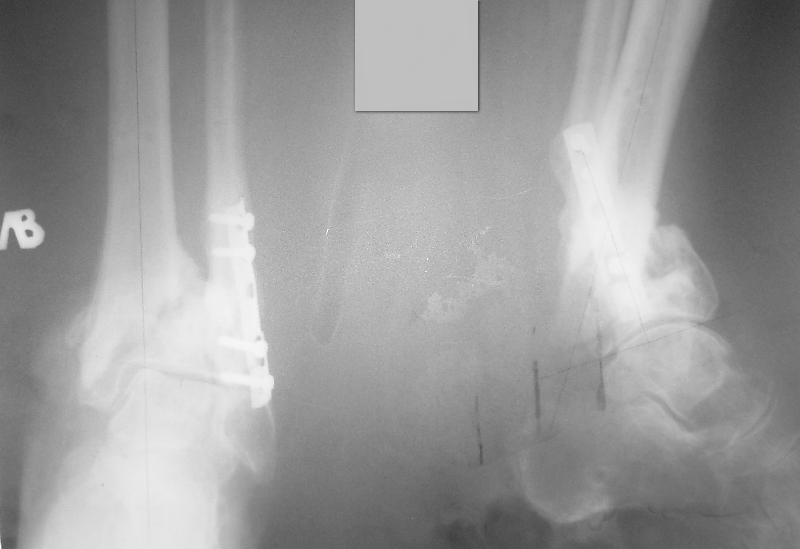

Женщина 72 л соматически сохранная, умеренно полная, в мае прошлого года получила бытовую травму - открытый оскольчатый внутрисуставной перелом дистального метаэпифиза большеберцовой кости (Gustilo III-A) и поперечный перелом н/з малоберцовой кости со смещением отломков. Оперирована ургентно - открытая репозиция отломков малоберцовой кости, остеосинтез пластиной. ПХО раны голеностопного сустава, стабилизация отломков большеберцовой кости стержневым аппаратом. Репозиция отломков удовлетворительная (варус до 5 гр, рекурвация до 5 гр) - сильно за ней не гонялись, много осколков. В дальнейшем заживление ран первичное. Аппарат до 3 мес, затем гипсовая лонгета. Общий срок иммобилизации и разгрузки нижней конечности 4,5 мес - разрешена нагрузка после клинических и рентгенологических? признаков сращения. Последние 4 мес из поля зрения выпала, появилась сегодня. Беспокоят сильные боли при ходьбе, деформация голени, хромота. Р-контроль прилагается - варус 16 гр, рекурвация 35 гр (прошу прощения за качество снимков). Клинически варусно-рекурвационная деформация н/з голени, подвижность в н/з, боль. Движения в голеностопном суставе разгибание-сгибание 0/0/20. Трофика не нарушена, рубец области медиальной лодыжки плотный, спаян с подлежащими тканями.

Больная хочет ходить без боли на ровной ноге (что вполне естественно). Возникает вопрос - как этого добиться?